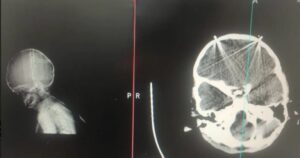

بر اساس تصاویر رادیوگرافی که به ایرانوایر رسیده است، یک نوزاد زیر یک سال در روز ۱۹ دیماه هدف شلیک گلولههای ساچمهای قرار گرفته است. این تصاویر نشان میدهند، دستکم ۹ ساچمه در سر این کودک وجود دارد. به گفته شاهدان عینی پدر این نوزاد که از اقلیتهای قومی است، پس از خرید در حالی که نوزاد در بغل او بوده و به منزل باز میگشته، با نیروهای امنیتی روبرو میشود. ماموری که یک تفنگ ساچمهپاش (شاتگان) در دست داشته، با وجود اینکه میبیند این مرد لوازم خرید به همراه دارد، ابتدا به او و سپس به بچه در بغل او نگاه میکند و تفنگ را مستقیم به سوی بچه شیرخوار نشانه رفته و او را هدف قرار میدهد.

انجمن مستقل جهانی پزشکان و کادر درمان ایران، آیفا، یکی از نهادهایی است که در سالهای گذشته به مجروحان اعتراضات یاری میرساند، هما فتحی یکی از اعضای این مجموعه، در مورد این پرونده تایید میکند که این کودک «شیرخوار» است. او شواهد مبنی بر شیرخوار بودن این نوزاد را اینگونه بیان میکند: «در تصاویر مشخص است که دندانهای او به شکل کامل در نیامدهاند و فونتانل جلویی [ناحیه نرم و جلویی بالای سر نوزاد] هنوز بسته نشده است و به طور قطع این بچه زیر ۱۸ ماه است و احتمالا در سال اول زندگیش به سر میبرد.»

هما فتحی در تشریح تصویر رادیو گرافی این نوزاد میگوید: «در سر او ۹ ساچمه دیده میشود، محل آنها عمدتاً در قسمت پیشانی سر است، ولی دو ساچمه در صورت است. احتمالا یکی در ته کاسهٔ چشم باشد و یکی در لبهٔ آن. به صورت دقیق نمیتوان گفت چشم آسیب دیده یا خیر، اما احتمال آن بالاست.»

فتحی در این زمینه میگوید: «با مواردی که میبینم به نظر میآید، ساچمه داخل کاسه چشم میتواند به نابینایی نوزاد منجر شود. در مورد ساچمههای دیگر که به جمجمه خوردهاند، اگر جمجمه قدرت کافی داشته باشد، امکان دارد در جمجمه گیر کنند. با این حال چون جمجمه نوزاد در حال رشد است، احتمال دارد در مرور زمان ساچمهها به داخل بافت جمجمه نفوذ کنند. به خصوص که در تصاویر دیده میشود که دو ساچمه استخوان جمجمه را سوراخ کردهاند و این ساچمهها میتوانند به عفونت مغزی منجر شوند که بسیار خطرناک هستند، مانند «مننژیت» یا «آنسفالیت»، که به یک نقطه محدود نشده و تمام مغز را درگیر میکنند و میتواند به مرگ، از دست رفتن تفکر هوشمندانه، فلج یا عدم تکلم نوزاد منجر شود.»

در تصاویر همچنین دو ساچمه روی لبههای ناحیه فونتانل هستند. این ساچمهها چه خطری را متوجه نوزاد می کنند؟ این فعال کادر درمان پاسخ میدهد: «چون در آن قسمت جمجمه، استخوان هنوز شکل نگرفته است و در حال تکمیل است، پردهٔ مغزی بسیار نازکی در آنجا قرار دارد که ساچمه میتواند به راحتی داخل بافت مغز وارد شده و به عفونت منجر شود. از سوی دیگر امکان دارد وجود ساچمه در آن ناحیه به خونریزی و سکته مغزی منجر شود. در کمال تأسف با عکسهایی که میبینم این آسیبها میتوانند به مرگ، نابینایی یا ناتوانیهایی که تا آخر عمر همراه نوزاد باشند، منتهی شده و دستکم آیندهٔ او را تا آخر عمر تحت تأثیر قرار دهند.»